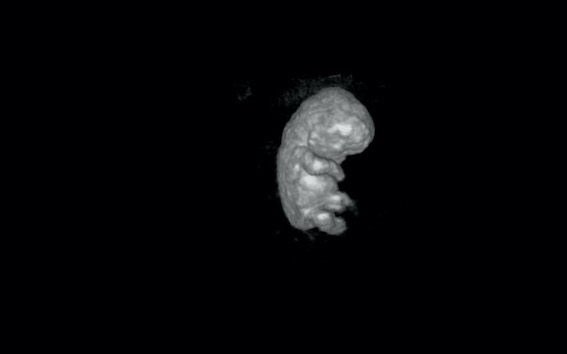

ROTTERDAM 27/03 Les embryons de grossesses qui se terminent par une fausse couche mettent plus de temps à se développer dans l'utérus que ceux des grossesses qui aboutissent à des naissances vivantes, selon une nouvelle étude publiée aujourd'hui dans Human Reproduction, l'une des principales revues de médecine reproductive au monde. Cette étude pourrait renforcer la prévention des fausses couches et une meilleure prise en charge de ses suites psychologiques.